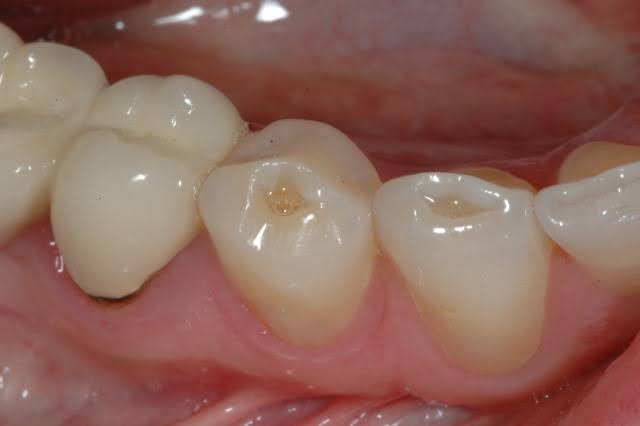

3. Teeth Grinding (Bruxism)

Chronic grinding or clenching puts excessive pressure on your teeth and supporting structures. Over time, this can weaken the attachment and lead to looseness.

This often happens during sleep, making it difficult to detect early.

Signs:

- Jaw pain or tightness

- Worn or flattened teeth

- Headaches

- Tooth sensitivity

Treatment:

- Night guard

- Bite adjustment

- Stress management